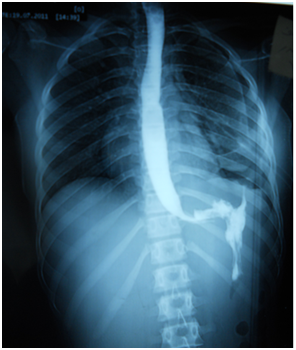

A 17-year-old girl (170cm, 60kg) presented to the emergency department with dyspnea and chest pain after a penetrating stab wound to the chest in the left sixth intercostal space mid-clavicular line, which happened 2hours earlier. Upon physical examination, Pulse was 96 beats per minute and blood pressure was 110/70mmHg, diminished air entry was noticed on the left side of chest. Chest x-ray revealed left hydropneumothorax. Tube thoracostomy was performed left intercostals tube was inserted for drainage. Post-insertion chest x-ray revealed no improvement in the picture of air fluid level (Figure 1) (Figure 2) which was further evaluated by CT that showed fluid collection posteriorly and air anteriorly (Figure 3) (Figure 4). Two days later patient had fever with vomiting and leucocytosis. The nature of the drain from the intercostal tube becomes serosangenous and less hemorrhagic with change in color associated with food. Methylene blue dye (1% concentration) taken orally by the patient was detected in the drain of the intercostal tube two minutes after ingestion (Figure 5). Oral contrast chest x-ray was done, two shots were taken one on swallowing gastrographin, it showed the esophagus outlined without any leakage (Figure 6A). The other shot taken two minutes after oral administration of gastrographin in trendlenberg position, the contrast outlined a track passing from the fundus of the stomach to the left pleural cavity and to the intercostals tube (Figures 6B) (Figure 6C). Laparotomy was performed via midline incision and findings were confirmed. It showed a 3cm orifice of the left copula of the diaphragm with a tear in the gastric fundus which was closed in two layers and the diaphragmatic tear was closed directly with continuous sutures. Two weeks later patient complicated by left empyema with thickened pleura. Thoracotomy was done for complete evacuation of pus and decortication. The patient fully recovered and was discharged 8days after thoracotomy.

Figure 6 A-C Chest X-ray with oral contrast showing connection between the stomach and the left pleural cavity.

The term thoraco-abdominal trauma is the best description of injuries located between a horizontal line passing through the nipples superiorly and costal margins inferiorly, as penetrating trauma injuries in that part of the body may involve both diaphragm and upper abdominal viscera due to their close relationship.4,5 Liver, diaphragm, spleen and stomach are the most frequently injured organs besides lungs, following penetrating thoraco-abdominal trauma like stab or bullet injury.5 Gastro-pleural fistula is a rare condition, in which there is an abnormal connection between stomach and pleural space, this may occur with or without diaphragmatic fistula. This condition can be caused by perforation of the intra-thoracic part of the stomach in cases of esophageal hiatal hernia. It can also be caused by trauma or erosion of an intra-abdominal abscess through the diaphragm.6 Radiological diagnosis of gastro-pleural fistula can be made using oral contrast, it can be confirmed by upper gastro-intestinal endoscopy and surgery to detect the exact site of the fistula. Ingestion of Methylene blue is an easy, fast, and simple way of diagnosis, also testing pleural fluid for pH or bile salts can be useful7–9 Penetrating stab wounds to the chest are rarely associated with gastro-pleural fistula. The described patient did not show any gas under diaphragm in erect chest x-ray or any free fluid in pelvi-abdominal ultrasound which means that the communication was strictly between the stomach and the pleural cavity with no intra-peritoneal involvement. Being such a rare condition, diagnosis of gastro-pleural fistula was very challenging especially with no radiological evidence of intra-abdominal injury. However, the presentation of gastro-intestinal symptoms with the noticed change in intercostal tube drain with feeding has guided us to perform the methylene blue test. The usefulness of methylene blue ingestion for early diagnosis of gastro-pleural fistula is demonstrated by this case, which is the key point for successful management. As surgical repair is the definitive treatment of this condition and it should be performed without any delay to avoid unfavorable outcomes.3